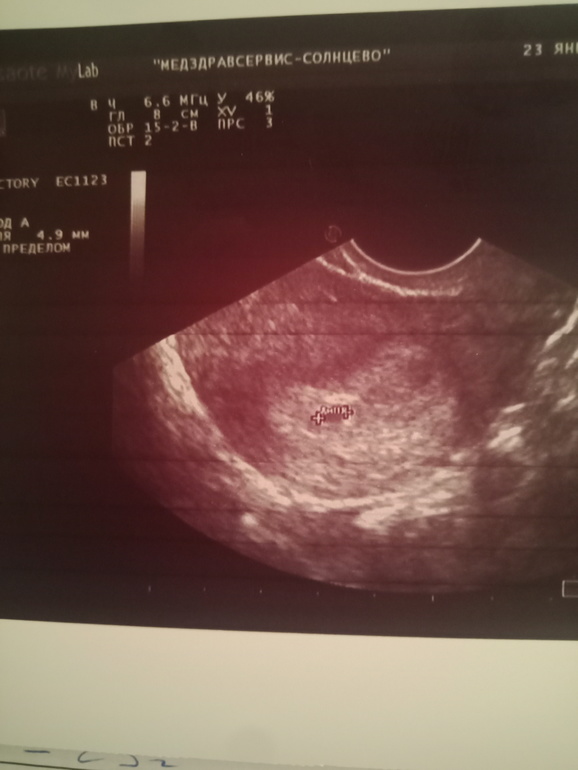

На мой непрофессиональный взгляд по передней, но матка в тонусе или сфоткано так..не буду утверждать, потом переделаете, расскажете))

Да. У меня тонус. Вот думаю, ехать на сохранение или дома с ношпой, папаверином и дюфастоном лежать